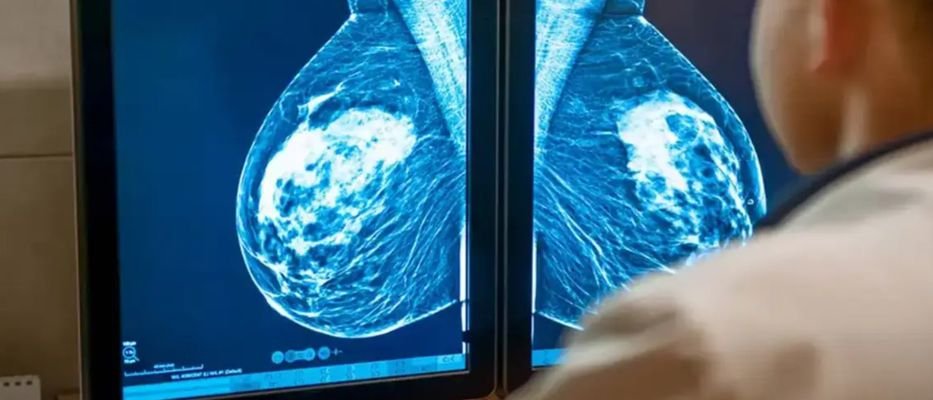

La detección temprana ha sido, durante décadas, el pilar fundamental en la lucha contra el cáncer de mama. Sin embargo, los sistemas de cribado tradicionales basados en la observación humana a menudo se enfrentan a limitaciones biológicas y técnicas, especialmente en el caso de los denominados «cánceres de intervalo», aquellos que aparecen entre una mamografía normal y la siguiente cita programada. El reciente avance del modelo de inteligencia artificial BRAIx marca un punto de inflexión, transformando la mamografía de una herramienta de diagnóstico actual a una potente ventana de predicción a largo plazo.

Históricamente, el éxito de un cribado dependía de encontrar una lesión ya existente. El modelo BRAIx, desarrollado por investigadores de la Universidad de Melbourne y validado en cohortes internacionales masivas, cambia las reglas del juego. No se limita a buscar tumores visibles; analiza patrones sutiles en el tejido mamario que son imperceptibles para el ojo humano, convirtiendo la imagen radiológica en una puntuación de riesgo personalizada.

Uno de los mayores retos en la radiología mamaria es la densidad del tejido. En mamas densas, el tejido glandular puede «ocultar» tumores en una mamografía convencional, elevando la tasa de falsos negativos. BRAIx ha demostrado ser excepcionalmente eficaz precisamente donde los métodos tradicionales fallan.

Al ser entrenado con más de 3,3 millones de imágenes, el algoritmo ha aprendido a identificar señales de riesgo que van más allá de los factores convencionales como la edad o los antecedentes familiares. Mientras que la densidad mamaria es un indicador general, BRAIx extrae características estructurales específicas que permiten predecir la aparición de tumores agresivos años antes de que se manifiesten clínicamente.